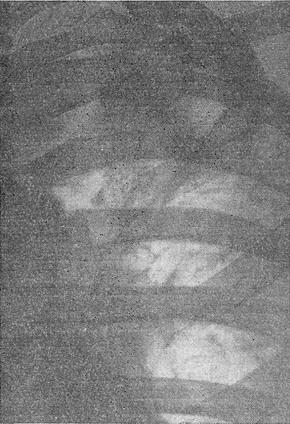

![]() Рис. 5. Туберкульозний лобит. |

Інфільтративно - пневмонічні форми відносяться до активних форм туберкульозу легень. Запальні зміни у вигляді округлого фокуса, званого інфільтратом (див.), що найчастіше розташовуються у підключичної зоні. Інфільтрат являє собою пневмонический вогнище з казеозним центром і тому схильний до утворення каверн, до бронхогенний і лімфогенного поширення (рис. 4); іноді процес захоплює цілу долю легені (туберкульозний лобит; рис. 5).